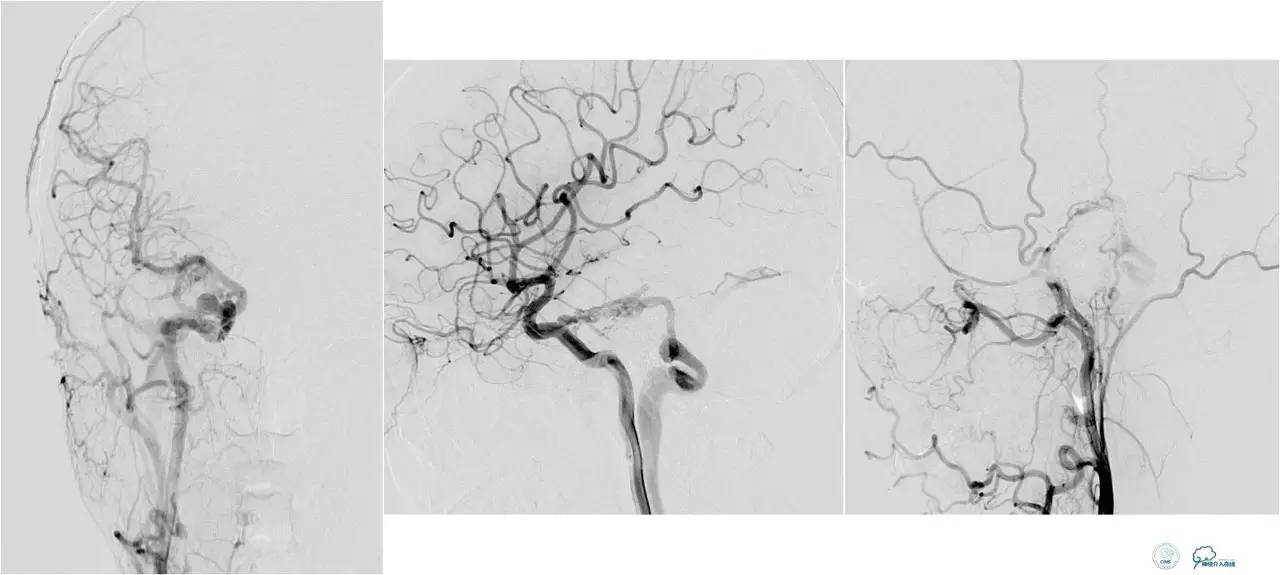

脑膜后动脉供血的小脑幕的瘘。

颈内不参与供血。

大脑后动脉有细小分支供血。

Sceptor球囊无法到达瘘口位置,放在主干内,充盈球囊后把动脉血管床内血液冲洗干净,形成楔入效果。

术后造影【Post embolization】